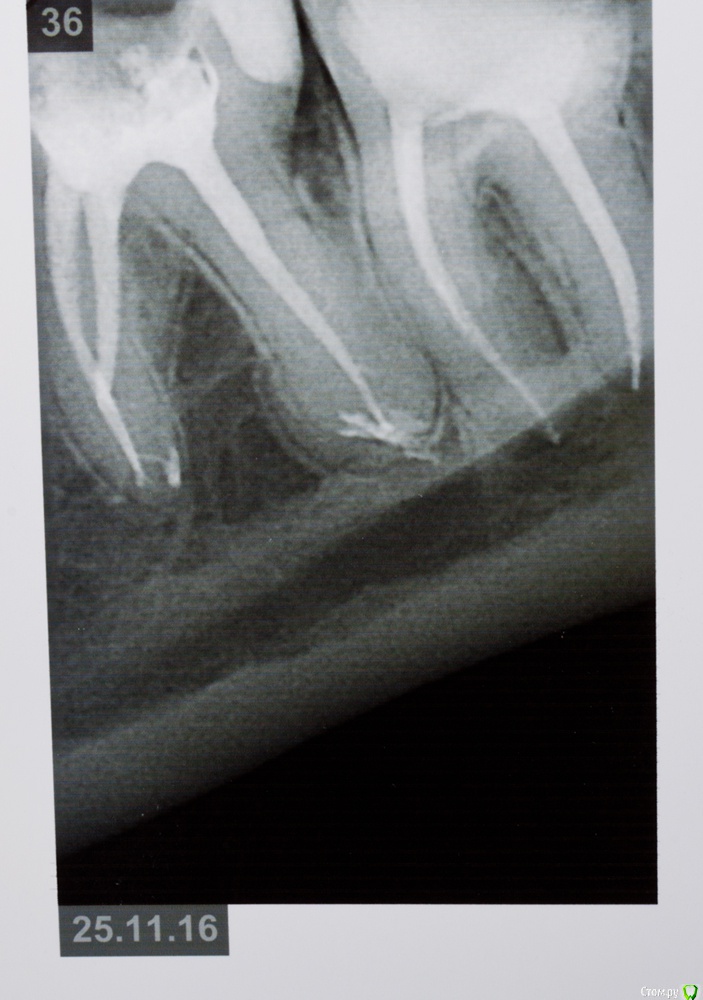

венди Опубликовано 26 января, 2017 Поделиться Опубликовано 26 января, 2017 (изменено) Добрый день! Не знаю в какой раздел будет правильно добавить, т.к. проблема смешанная. Помогите, пожалуйста! 3 месяца мучений. В прошлом году начала заниматься зубами. Был сделан панорамный снимок (прилагаю).В мае в районе отсутствующего 26 был установлен имплант с одновременным открытым синус-лифтингом. Послеоперационный период протекал более-менее нормально. Меня отпустили на пол года. И я стала заниматься остальными зубами. Лечили кариес справа, был удален 46 (резорбация мед. стенки медиального корня с перфорацией). К осени добрались до левой нижней стороны. 26.09. - был залечен кариес в 36 зубе. После этого зуб стал стрелять током при накусывании. Врач решила ещё понаблюдать.19.10. - 37 зуб с гранулемой был распломбирован, врач прошла каналы, заложила кальций. Через 6 дней ещё раз все прочистили, запломбировали каналы полностью, поставили временную пломбу и сказали, что можно протезироваться. Вроде зуб после лечения не беспокоил.01.11. - я пошла на осмотр к хирургу по поводу удаленного 46. Хирург решил раскрыть имплант, т.к. уже время подошло. Сказал всё хорошо прижилось и поставил формирователь десны. С этого дня моя жизнь разделилась на до и после.. Стала болеть вся область вокруг импланта, появилось ощущение мешающего валика под щекой, формирователь утонул в десне, отечность в этой области была. Обобщу и скажу, что после этого формирователь перекручивался еще 3 раза, внутри все промывалось, я принимала антибиотики. Острые ощущения немного ушли, но дискомфорт мешающий нормально жить оставался. По снимку - все отлично, имплант интегрирован (прилагаю). Одновременно с этими манипуляциями с имплантом 36 зуб стал не только бить током, а до него уже нельзя было дотронуться. 18.11 - вскрыли, депульпировали, заложили кальций и через неделю закрыли все постоянной пломбой (снимок прилагаю). Всё это время, впрочем как и сейчас вся левая сторона была охвачена ужасными ощущениями. Распирание, нытье, давящая боль, дискомфорт и днем и ночью. Стала плохо спать. Перед Новым Годом хирург принял решение выкрутить формирователь и посмотреть за динамикой. Мне показалось, что стало немного легче, особенно что касается ощущение валика под щекой. НО все равно с левой стороны мне что-то болит. От области импланта ли это идет или от 36-37 - я не знаю, не могу точно дифференцировать.... т.к. ковырялись везде одновременно и у меня уже все спутано... Никто не может понять, что со мной, т.к. по снимкам и 3Д все отлично. На прошлой неделе придя в очередной раз в клинику - по панорамному снимку и моим жалобам на боли поставили диагноз "дисфункция ВНЧ, артроз ВНЧС слева". При этом я спокойно открываю рот без болей, щелчков и хруста, при жевании тоже ничего не болит. Назначили физио и Аэртал - принимаю больше недели вообще все без изменений... аэртал даже не обезбаливает особо. На данный момент я ощущаю постоянный тупой ноющий тянущий дискомфорт слева. Чувство распирания. Поднимается иногда температура 37-37,1. Плохо сплю, нервничаю, т.к. очень снизилось качество жизни. Помогите, пожалуйста, разобраться. На что бить, если по снимками как бы все хорошо?! Имплант, 36, 37, сустав?? Все началось с раскрытия имланта. До этого я жила обычной жизнью. Есть 3Д декабрьские. Если кто-то захочет посмотреть я добавлю. Спасибо! Изменено 26 января, 2017 пользователем венди Ссылка на комментарий